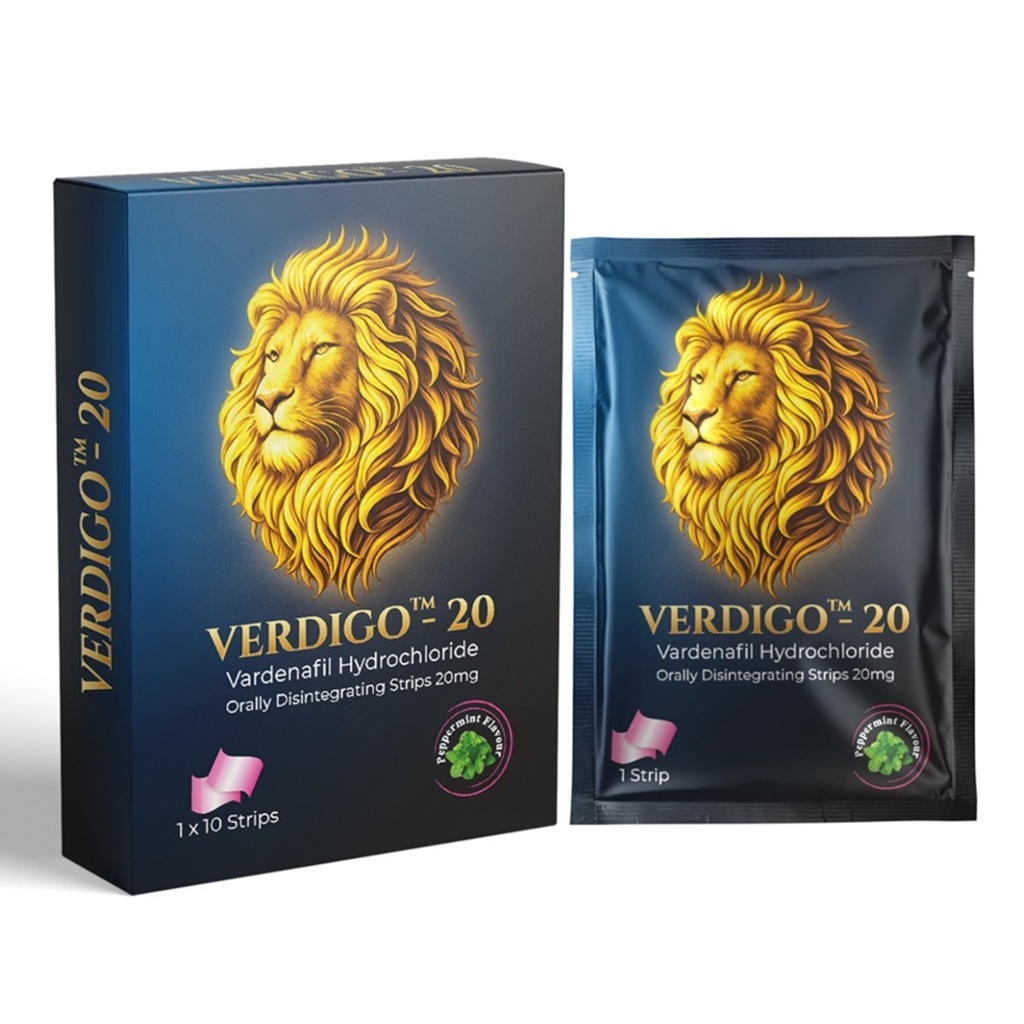

Medicinal or Drug Products

Strips Are Fortune Strips For The Patients Who Suffer From Erectile Dysfunction. These Strips Are A Perfect Re-Placement For Pills, Jelly And Chewable. By Unique Formulations The Active Ingredient Sildenafil Citrate Is Absorbed Via The Oral Mucosa And Directly Enters The Systemic Circulation Which Works Faster When Compared To Other Dosage Forms When Absorbed Through The Stomach.

Medicinal or Drug Products

Strips Are Fortune Strips For The Patients Who Suffer From Erectile Dysfunction. These Strips Are A Perfect Re-Placement For Pills, Jelly And Chewable. By Unique Formulations The Active Ingredient Sildenafil Citrate Is Absorbed Via The Oral Mucosa And Directly Enters The Systemic Circulation Which Works Faster When Compared To Other Dosage Forms When Absorbed Through The Stomach.